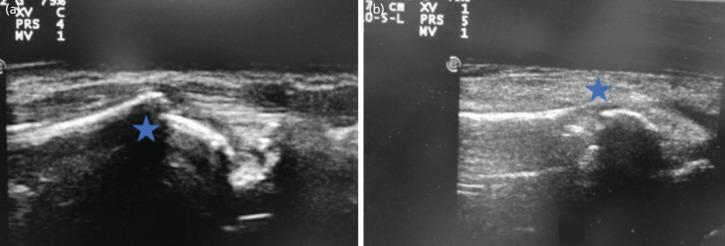

Introduction: Ultrasound-guided manipulation and reduction (M&R) of the distal radius fractures (DRF) is believed to improve radiographic indices due to real-time feedback of fracture alignment. The objective of this trial was to compare volar tilt, radial inclination, and radial height on radiographs between Ultrasound guided and conventional (landmark-guided) M&R.

Materials and methods: A total of 79 distal radius extraarticular fractures in adults were randomised to Ultrasound guided and conventional (landmark-guided) M&R. The radiograph parameters described above were compared before and after M&R in both groups.